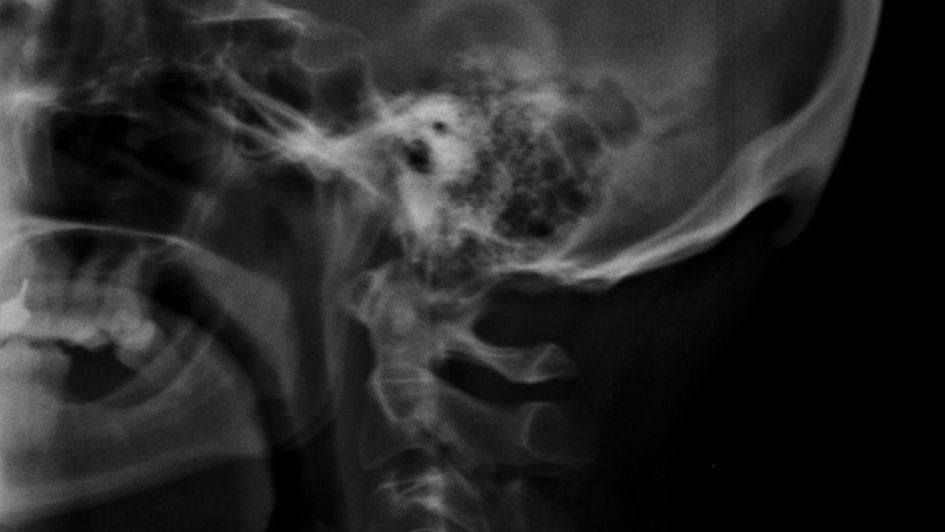

Los investigadores realizaron el hallazgo de una protuberancia, como una espina, en pleno cráneo humano, lo que estaría directamente relacionado con la dependencia a los teléfonos móviles.

El estudio involucró 2.018 rayos X de personas entre 18 a 30 años en la costa de Australia, encontrando que el 41% desarrolló un hueso detrás del cráneo de unos 10 a 30 milímetros. Este hueso crece por la posición que el ser humano emplea para mirar el celular, con la cabeza un poco inclinada hacia adelante, consigna Clarín.

Este hueso era exclusivo en pacientes de mayor edad, por lo que resulta increíble que lo estén desarrollando personas jóvenes. «Es importante entender que en la mayoría de los casos, el hueso se desarrolla unos pocos milímetros, pero las proyecciones indicaron que ya existen huesos entre 10 a 30 milímetros en la población joven», comentó David Shahar, uno de los investigadores.